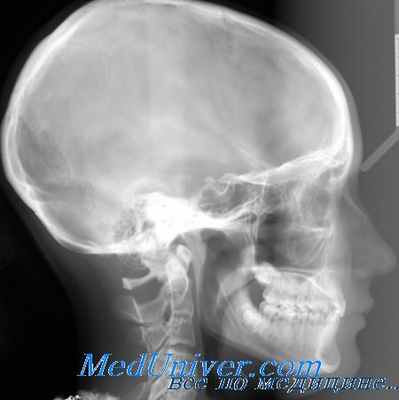

Диагноз ставят на основании характерной клинической картины. Бурное начало, быстрое прогрессирование и тяжелое течение отличают флегмону орбиты от тенонита. Необходима рентгенография придаточных пазух носа и глазницы, которая имеет значение для дифференциального диагноза флегмоны глазницы от периостита орбитальной стенки, а также для исключения инородного тела глазницы при травме.

Рентгенологическое исследование при флегмоне глазницы следует признагь необходимым и обязательным. Поскольку флегмона глазницы представляет собой в основном тромбофлебит с образованием гнойных абсцессов в жировой клетчатке, на рентгенограмме (полуаксиальпый снимок глазниц) обнаруживают большей частью более или менее выраженное затемнение соответствующей глазницы, обычно диффузного характера. Такое затемнение может наблюдаться и при теноните (воспаление теноновой сумки). Однако клиническая картина тенопита отличается от флегмоны глазницы тем, что в первом случае экзофталм менее выражен, а хемоз сильнее.

Провести диференциальный диагноз с помощью рентгенологического исследования трудно, все же следует знать, что при теноните затемнение глазницы менее интенсивно, чем при флегмоне. Диффузное затемнение глазницы может наблюдаться и при ретробульбарной опухоли, однако уже сама клиническая картина позволяет в большинстве этих случаев установить правильный диагноз.

Известные трудности возникают, когда процесс протекает более вяло. В таких случаях необходимо подумать о возможности периостита орбитальной стенки. В последнем случае клинически отмечается смещение глазного яблока в сторону; рентгенологически при этом определяется частичное затемнение глазницы соответственно пораженной стенке; на технически хорошо выполненной рентгенограмме видна также стушеванность структуры костной стенки.

Изменения в костных стенках глазницы при флегмоне наблюдаются редко. Тем не менее все же описаны случаи вскрытия флегмоны в полость черепа через верхнюю стенку глазницы. Следовательно, при рентгенологическом исследовании должно быть обращено сугубое внимание и на состояние костных стенок глазницы. Наличие узур, особенно в области верхней стенки глазницы, является грозным признаком возможного прорыва флегмоны в полость черепа. Отрицательный результат рентгенологического исследования не говорит еще об отсутствии нарушения целости той или другой костной стенки глазницы. Как уже указывалось, строение глазницы, тонкость ее стенок создают мало благоприятные условия для рентгенологического исследования.

Естественно, что при рентгенологическом исследовании необходимо обратить внимание на наличие в глазнице инородных тел. Металлические осколки определяются легко, но нередко флегмона глазницы может быть обусловлена проникновением инородных тел, дающих мало интенсивную тень, как, например, дерево, стекло и т. д. На технически хорошо выполненных рентгенограммах в таких случаях иногда можно обнаружить едва диференцируемую тень инородного тела.

Довольно часто флегмона глазницы обусловлена переходом воспаления со смежных областей. В детском возрасте флегмона глазницы нередко может быть вызвана остеомиэлитом верхней челюсти. Источником инфекции могут быть и зубы. Особенно часто флегмона глазницы развивается в результате воспаления придаточных полостей носа. По данным ряда авторов (С. И. Тальковский, Бирх-Гиршфельд и др.), флегмона орбиты по своему происхождению наиболее часто связана с эмпиемой придаточных полостей носа.

Периорбита тесно соединена с подлежащей костью только в области краев глазницы, у ее вершины и в области швов; на всем же остальном протяжении соединение это довольно рыхлое, вследствие чего периорбита легко отслаивается. Это способствует тому, что при воспалении придаточной полости носа часто образуется субпериостальный абсцесс с переходом воспалительного процесса на орбитальную клетчатку. При рентгенологическом исследовании это обстоятельство нужно учитывать.

Изучая рентгенограммы, необходимо обратить внимание на смежные с глазницей области, особенно на придаточные полости носа. Во многих случаях удается таким образом определить своевременно причину заболевания и применить необходимое лечение.